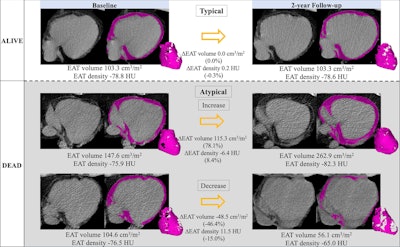

Epicardial adipose tissue (EAT) segmentation (shading) at noncontrast chest CT in axial orientation. Representative examples show EAT changes (ΔEAT) between baseline and two-year follow-up CT scans in participants who survived (typical changes) and increasing and decreasing EAT in participants who died. Images and caption courtesy of the RSNA.

The researchers categorized EAT volume and density over two years into the following: typical changes, a decrease of 7% to an increase of 11% and decrease of 3% to increase of 2%, respectively; and atypical changes, increases, or decreases beyond typical ones.

Among the total participants, 3,483 (16.9%) died over a median follow-up of 10.4 years. Of these deaths, 816 (23.4%) were cardiovascular-related and 705 (20.2%) were lung cancer-related.

The researchers reported the following findings in relation to EAT changes:

- Average epicardial adipose tissue volume increased (2.5 cm3/m2) and density decreased (decrease of 0.5 Hounsfield units) over two years.

- Atypical changes in EAT volume were independent predictors of all-cause mortality. For atypical increase, the hazard ratio (HR) was 1.15 (p < 0.001); for atypical decrease, the HR was 1.34 (p < 0.001).

- An atypical decrease in epicardial adipose tissue volume was significantly tied to cardiovascular mortality (HR, 1.27; p = 0.009).

- EAT density increase was significantly linked to the following mortality types: all-cause (HR, 1.29; p < 0.001), cardiovascular (HR, 1.29; p = 0.005), and lung cancer (HR, 1.3; p = 0.007).